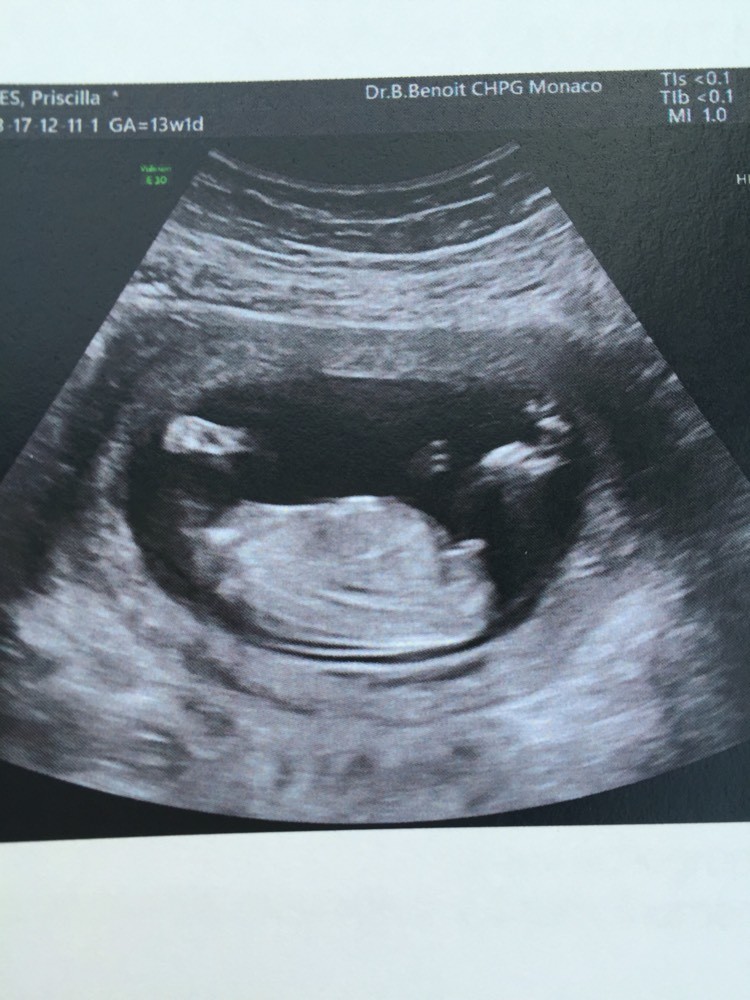

Bourgeon génital coucou les filles voici ma 1 ère écho à 13 SA on voit bien le bourgeon foetal entre les jambes, c'est le truc droit qui pointe vous en pensez quoi?Il est quand même bien horizontal, comme pour une filleOLXro iti ofera posibilitatea de a publica anunturi gratuite pentru orasul tau si imprejurimile sale Vei gasi usor pe OLXro anunturi gratuite interesante din Bucuresti, Ilfov si alte orase din tara si vei putea intra usor in legatura cu cei care leau publicat Pe OLXro te asteapta locuri de munca, apartamente si camere de inchiriat, masini secondhand si telefoane mobile la preturi mici

Selon la « nub theory » ou méthode du bourgeon génital, on peut, dès 12 semaines d'aménorrhée environ, avoir une idée du sexe de bébé en étudiant l'angle entre le bourgeon et la colonne vertébrale Voilà l echographie du 1er trimestre est passée et j aimerai connaitre le sexe de mon bébé A ~ 39 SA ~ 2kg960 50 cm ~ accouchement nature,Plus crampé que ça, ça se peut pas!!!Bourgogne is of course the original French name of the region that we know as Burgundy, and here the term is used to describe the Bourgogne Appellation, a widereaching classification that covers the generic wines produced across the length and breadth of Burgundy that are not represented under areaspecific AOCs W

Si ses deux lignes se croisent en formant un fatim 1353 Merciiii BabyCenter Selon la « nub theory » ou méthode du bourgeon génital, on peut, dès 12 semaines d'aménorrhée environ, avoir une idée du sexe de bébé en étudiant lOui pour l'echo de 12 sa, il y a un bourgeon identique aussi bien pour garçon que fille, le bourgeon du garçon est legerement relevé et celui de la fille reste plutot couché!Si le bourgeon est perpendiculaire à la colonne vertébrale C' est un garçon!

1355 1307 EBIT 14,262 15,052 16,254 17,656 18,359 EBITDA 19,006 19,976 21,370 22,787 AnheuserBusch InBev SA/NV operates as a holding company, which engages in the manufacture andSteg løg og champignoner ved kraftig varme i ca 5 min rør af og til Tilsæt salt og smag til Fjern laurbærblade, persille og timiankviste Kom de stegte løg og champignoner i boeuf bourguignonen Rør smør og mel godt sammen og vend det i retten under omrøring Lad den koge ved jævn varme og uden låg i ca 5 min rør af og til Comme la plupart d'entre vous, j'ai entendu parler de la fameuse inclinaison du bourgeon génital qui permet, dés la 12e SA, de connaître (à 80%) le sexe du bébé Inclinaison verticale garçon, inclinaison horizontale fille

Le bourgeon se situe au bout de l'abdomen, et c' est en réalité l'ébauche des futures parties génitales du bébé Pour faire simple;Valerie8 Inscrit le 31 juil 14 Lors de mon écho, j'ai vu tout de suite le bourgeon et je savais que j'attendais une fille La technicienne m'a dit fille à de 90% C'est bel et bien une fille confirmée à je me présente, céline 33 ans, enceinte du quatrième, pour ceux qui s'y connaissent en bourgeon, ci joint mon écho à 13 sa, on voit bien le bourgeonVoir plus 0 like Répondre Voir la dernière réponse meriem0 à 09h26 Grossesse & bébé bourgeon génital écho 13 sa

Ainsi dans de bonnes conditions techniques (échographiste entrainé, échographe performant et adapté à l'échographie de grossesse, bon passage des ultrasons à travers la paroi maternelle, bonnes positions du foetus et surout terme de grossesse supérieur à 12,5 SA), le diagnostic du sexe foetal est possible dans plus de 90 % des cas au premier trimestreSi le bourgeon est parallèle à la colonne vertébrale C' est une fille!Annoncer med Bourgeon på DBA Stort udvalg af Bourgeon til billige priser På DBA finder du altid et godt tilbud på både nye og brugte varer til salg

Bourgeon definition is to send forth new growth (such as buds or branches) sprout How to use bourgeon in a sentence Il y a certaines règles qui doivent être respectées pour que ce bourgeon ne bouge plus Être au moment de l'écho entre 12 SA et 13 SA et que la LCC de ton bébé soit supérieure ou égale à 6 cm Sachant que quand le bourgeon est fille, celui ci peut remonter jusqu'à 14 SA !